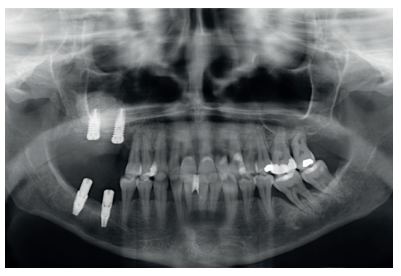

Finally, the stability of both treatments can be seen in the final X-ray at 8 years of age, where both are stable without bone loss (Figure 13).